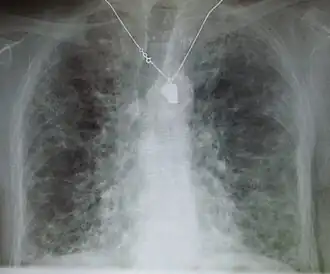

Lung

Side effects of oral amiodarone at doses of 400 mg or higher include various pulmonary effects.[44] The most serious reaction is interstitial lung disease. Risk factors include high cumulative dose, more than 400 milligrams per day, duration over two months, increased age, and preexisting pulmonary disease. Some individuals were noted to develop pulmonary fibrosis after a week of treatment, while others did not develop it after years of continuous use.[44] Common practice is to avoid the agent if possible in individuals with decreased lung function.

The most specific test of pulmonary toxicity due to amiodarone is a dramatically decreased DLCO noted on pulmonary function testing.